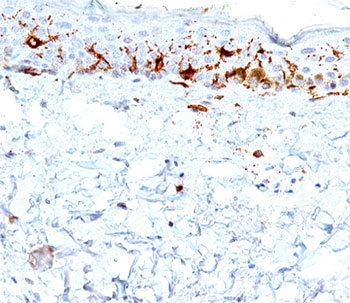

CD1A Antibody for IHC. Immunohistochemistry analysis of CD1A / CD1a expression in FFPE human skin tissue using CD1A Antibody. Membranous and cytoplasmic staining is observed in scattered dendritic cells within the epidermis, consistent with Langerhans cell localization, while surrounding keratinocytes remain largely negative. The distribution of CD1a-positive cells along the epithelial layer supports identification of antigen-presenting dendritic cells involved in local immune surveillance within skin.

CD1A Antibody for IHC. Immunohistochemistry analysis of CD1A / CD1a expression in human skin tissue using CD1A Antibody. Membranous and cytoplasmic staining is observed in dendritic cells within the epidermis, consistent with Langerhans cell localization, while surrounding keratinocytes remain largely negative. The distribution of CD1a-positive cells highlights antigen-presenting dendritic cells positioned at the epithelial interface, supporting evaluation of immune activation and antigen presentation within skin.